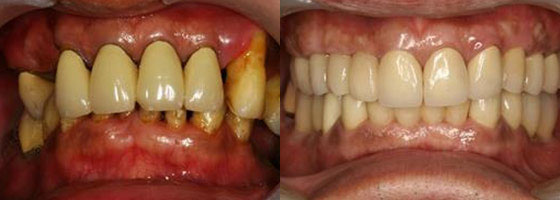

治療前VS.治療後。

病患恢復自信笑容。